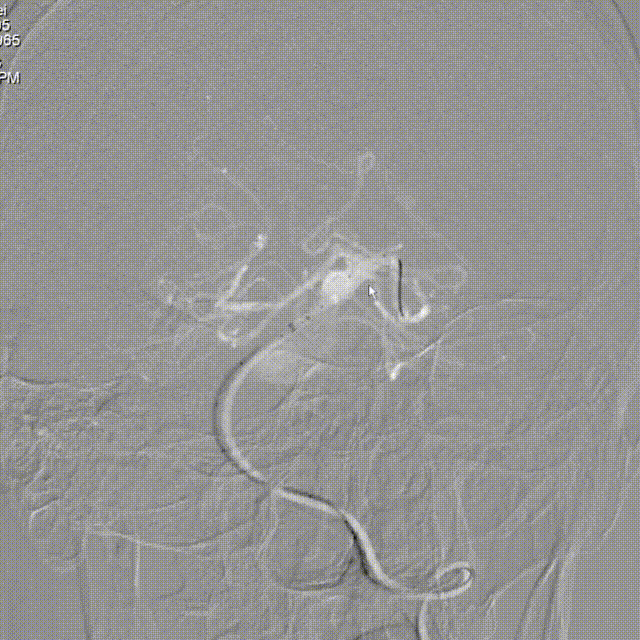

Lattice血流导向密网支架 5.3mm*41mm输送到位。

Lattice血流导向密网支架 5.3mm*41mm头端释放。

Lattice支架头端定位:

造影确认支架头端位置。

重回收调整支架头端定位。

Lattice支架中段释放:

造影确认支架头端避开PCA。

继续释放支架中段。

Lattice支架近端释放:

造影确认支架打开贴壁良好。

Lattice支架完全释放:

解脱前造影。

撤微导管完全释放。

Lattice支架后处理:

J型导丝按摩。

术后即刻造影。